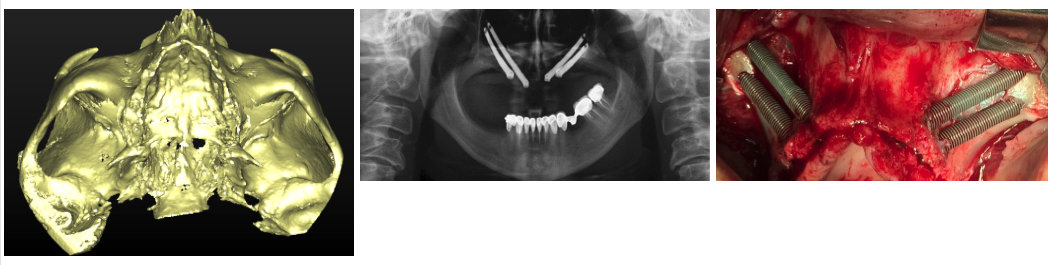

Paciente que precisa rehabilitación y presenta gran atrofia maxilar resuelta con la colocación de 4 implantes zigomáticos.

La planificación fue totalmente digital y los modelos fueron escaneados en 3D. La rehabilitación final ha sido en metal cerámica.

Vista de la planificación 3D, la rx con los zigomas colocados y de la cirugía de colocación de los implantes.